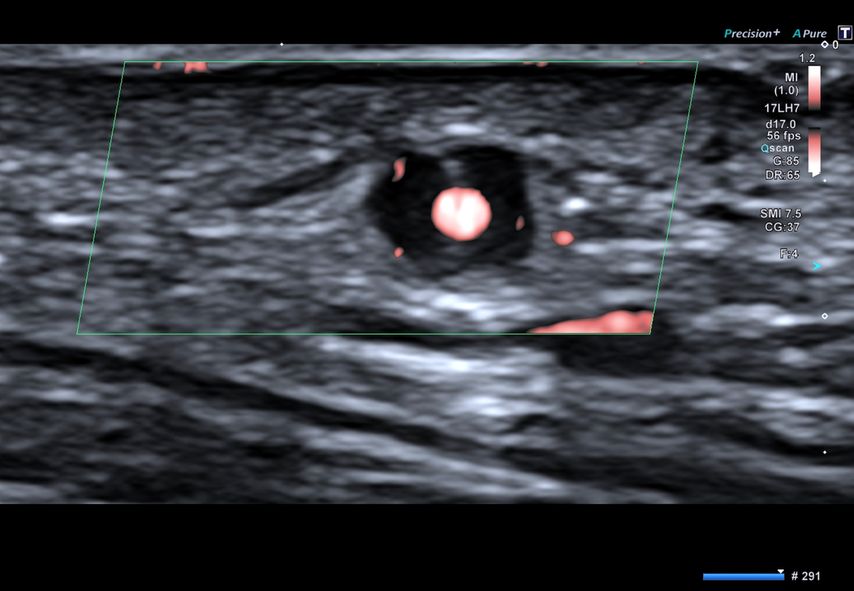

Abb. 1: Ultraschallbild einer Arteria temporalis eines Patienten mit Riesenzellarteriitis im Querschnitt. Dargestellt ist das charakteristische „Halo“-Phänomen, das der entzündlichen Schwellung der Arterienwand entspricht